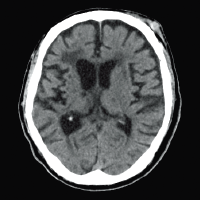

Клинические изображения

Для снижения лучевой нагрузки и повышения качества визуализации в КТ SUPRIA используются алгоритм интеллектуального перераспределения дозы IntelliEC и современный метод итерации IntelliIP, позволяющие провести сканирование с очень низкими значениями доз и получить изображения необходимого диагностического качества. В результате лучевая нагрузка на исследуемую область существенно снижается при сохранении высокого качества визуализации, особенно на уровне плотных паренхиматозных органов.